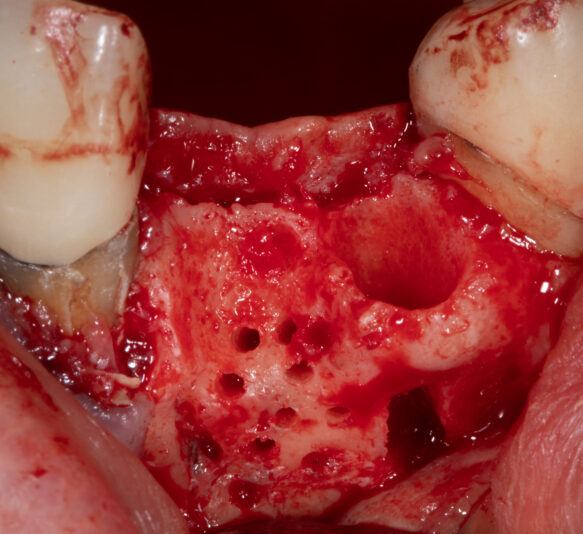

There was two failing anterior incisors with significant infection that had to be removed and we placed two immediate implants into sites with severe bony defects. We performed simultaneously GBR/GTR using CGF/PRF protocols. After 6 months of healing we fortunately had a great outcome with ample bone.

There’s always a nervous excitement when…